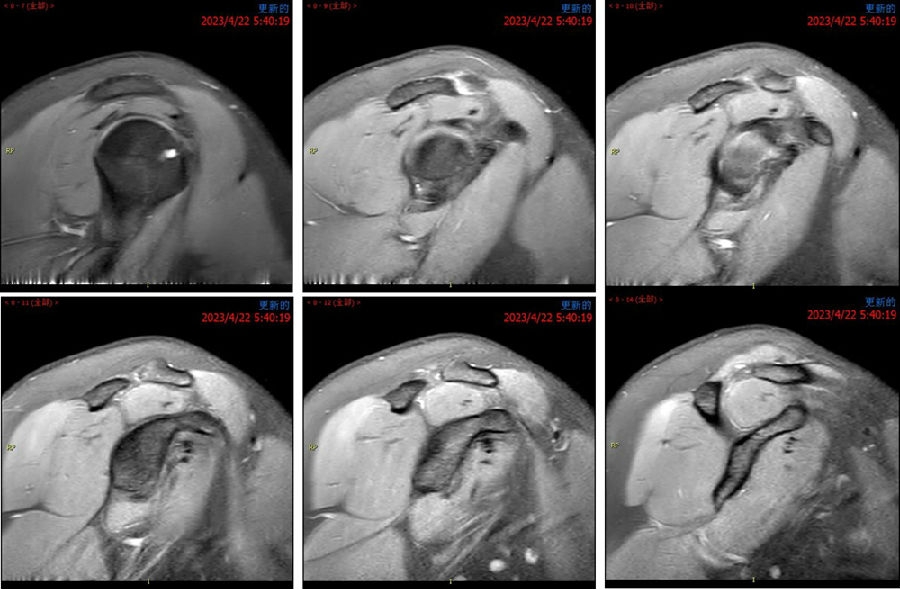

Case1:影像学评估病例,19岁,打篮球摔伤脱位。

图23 首次脱位

图24 打球再次受伤,复发脱位

图 25-27 MRI

双侧CT三维扫描显示:健侧肩胛盂宽度D=25.9,患侧D=23.9,患侧肩胛盂骨性缺损d=6.2,骨性盂唇缺损面积d/D为23.9%(<25%)。肩胛盂轨迹GT(83%D-d)为15.3mm。

图28双侧CT三维扫描

图29 Hill-Sachs间隙为13.8mm(<15.3mm)

图30 评估结果

评估报告提示:右肩胛骨关节盂前下缘撕脱骨折,符合骨性bankart损伤。右肱骨头后上缘凹陷骨折,符合Hill-Sachs损伤。Hill-Sachs间隙为13.8mm(<15.3mm),为轨迹内肩关节前脱位。